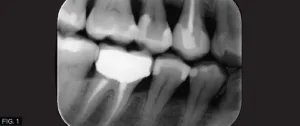

A young female physician presented to my office with a chief complaint of sensitivity to cold and sweets in her lower right dentition which has been persistent for approximately 1 month. Upon clinical and radiographic examination, it was determined that her lower right first premolar #28 (#44) had a previous restoration that had fractured and was compromised by recurrent caries. (FIG. 1)

The carious lesion was rather deep into the tooth according to the radiographic image but not wide. The carious lesion was less than ½ the distance between the buccal/lingual cusp distance making this an excellent case for a direct composite restoration. (FIG. 2)